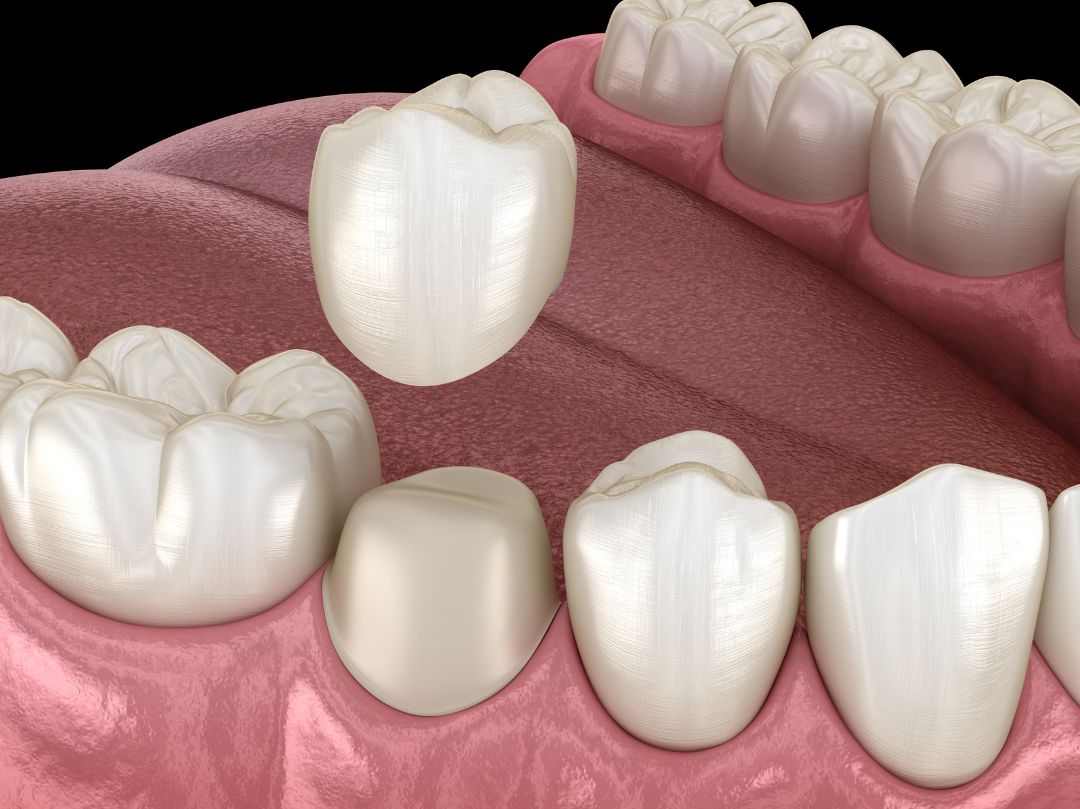

Couronne

Une couronne peut servir à couvrir la partie endommagée de votre dent et à protéger cette dernière contre d’autre dommage.

On peut en avoir besoin dans les cas suivants:

-après un traitement de canal;

-une grosse obturation dans une dent;

-une dent cassée;

-une dent décolorée, de forme inadéquate ou désalignée.

Les couronnes sont faites de divers types de métaux, de porcelaine ou d’un alliage céramo-métallique. Elles sont solides et durent environ 15 ans si vous en prenez bien soin. Brossez-les et passez-y la soie dentaire comme vous faites pour vos dents naturelles.